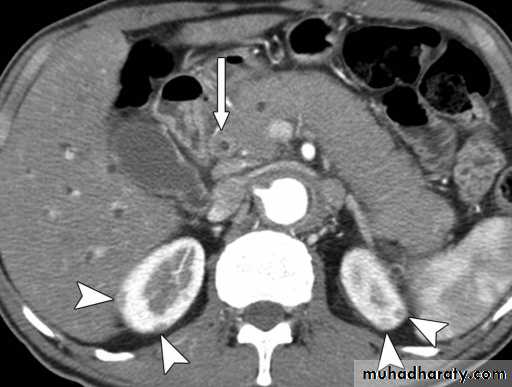

Appear as large oval hypo dense area density of fluid with well defined margin , sometime at their periphery multiple flecks of calcification are seen at their periphery .

Hydatid cyst with daughter cyst , appear as multiple hypo densities rounded area within the main loculi with multiple rim of

calcification